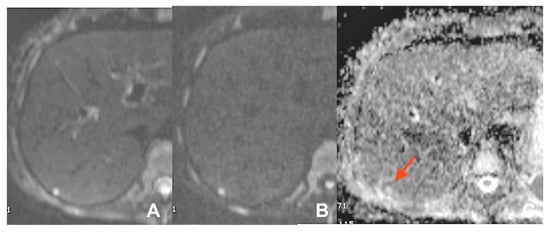

| DWI b 0–50–400–800 | AXIAL | -- | -- | Abscess in ADC map is hypointense | |

| DWI b 0–50–400–800 | AXIAL | -- | Infected collections appear hypointense in the ADC map | |